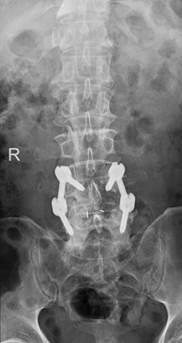

术后影像显示,螺钉位置良好